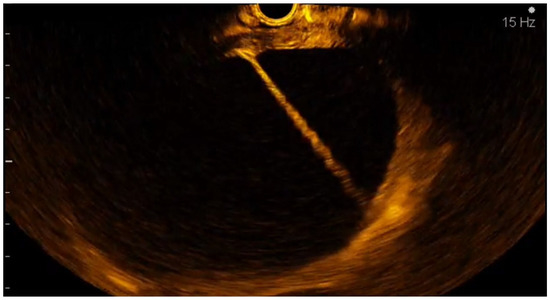

2.5. CE-EUS Procedure

- the contribution of associating CE-EUS with EUS-FNB for differentiating solid pancreatic lesions without on-site cytopathology

3.2. EUS-FNA/FNB + CE-EUS of Solid Pancreatic Lesions Subgroup